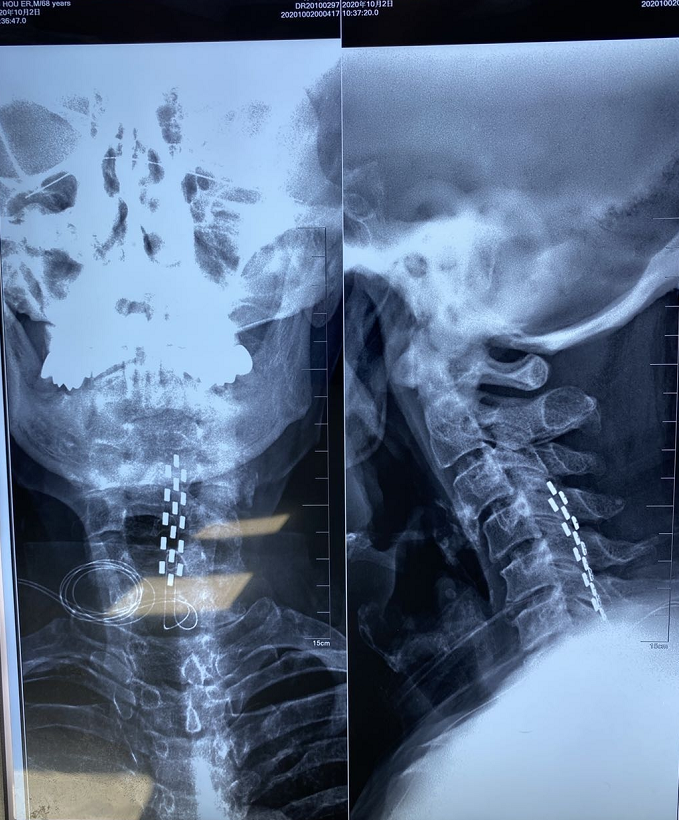

影像结果显示:电极有移位